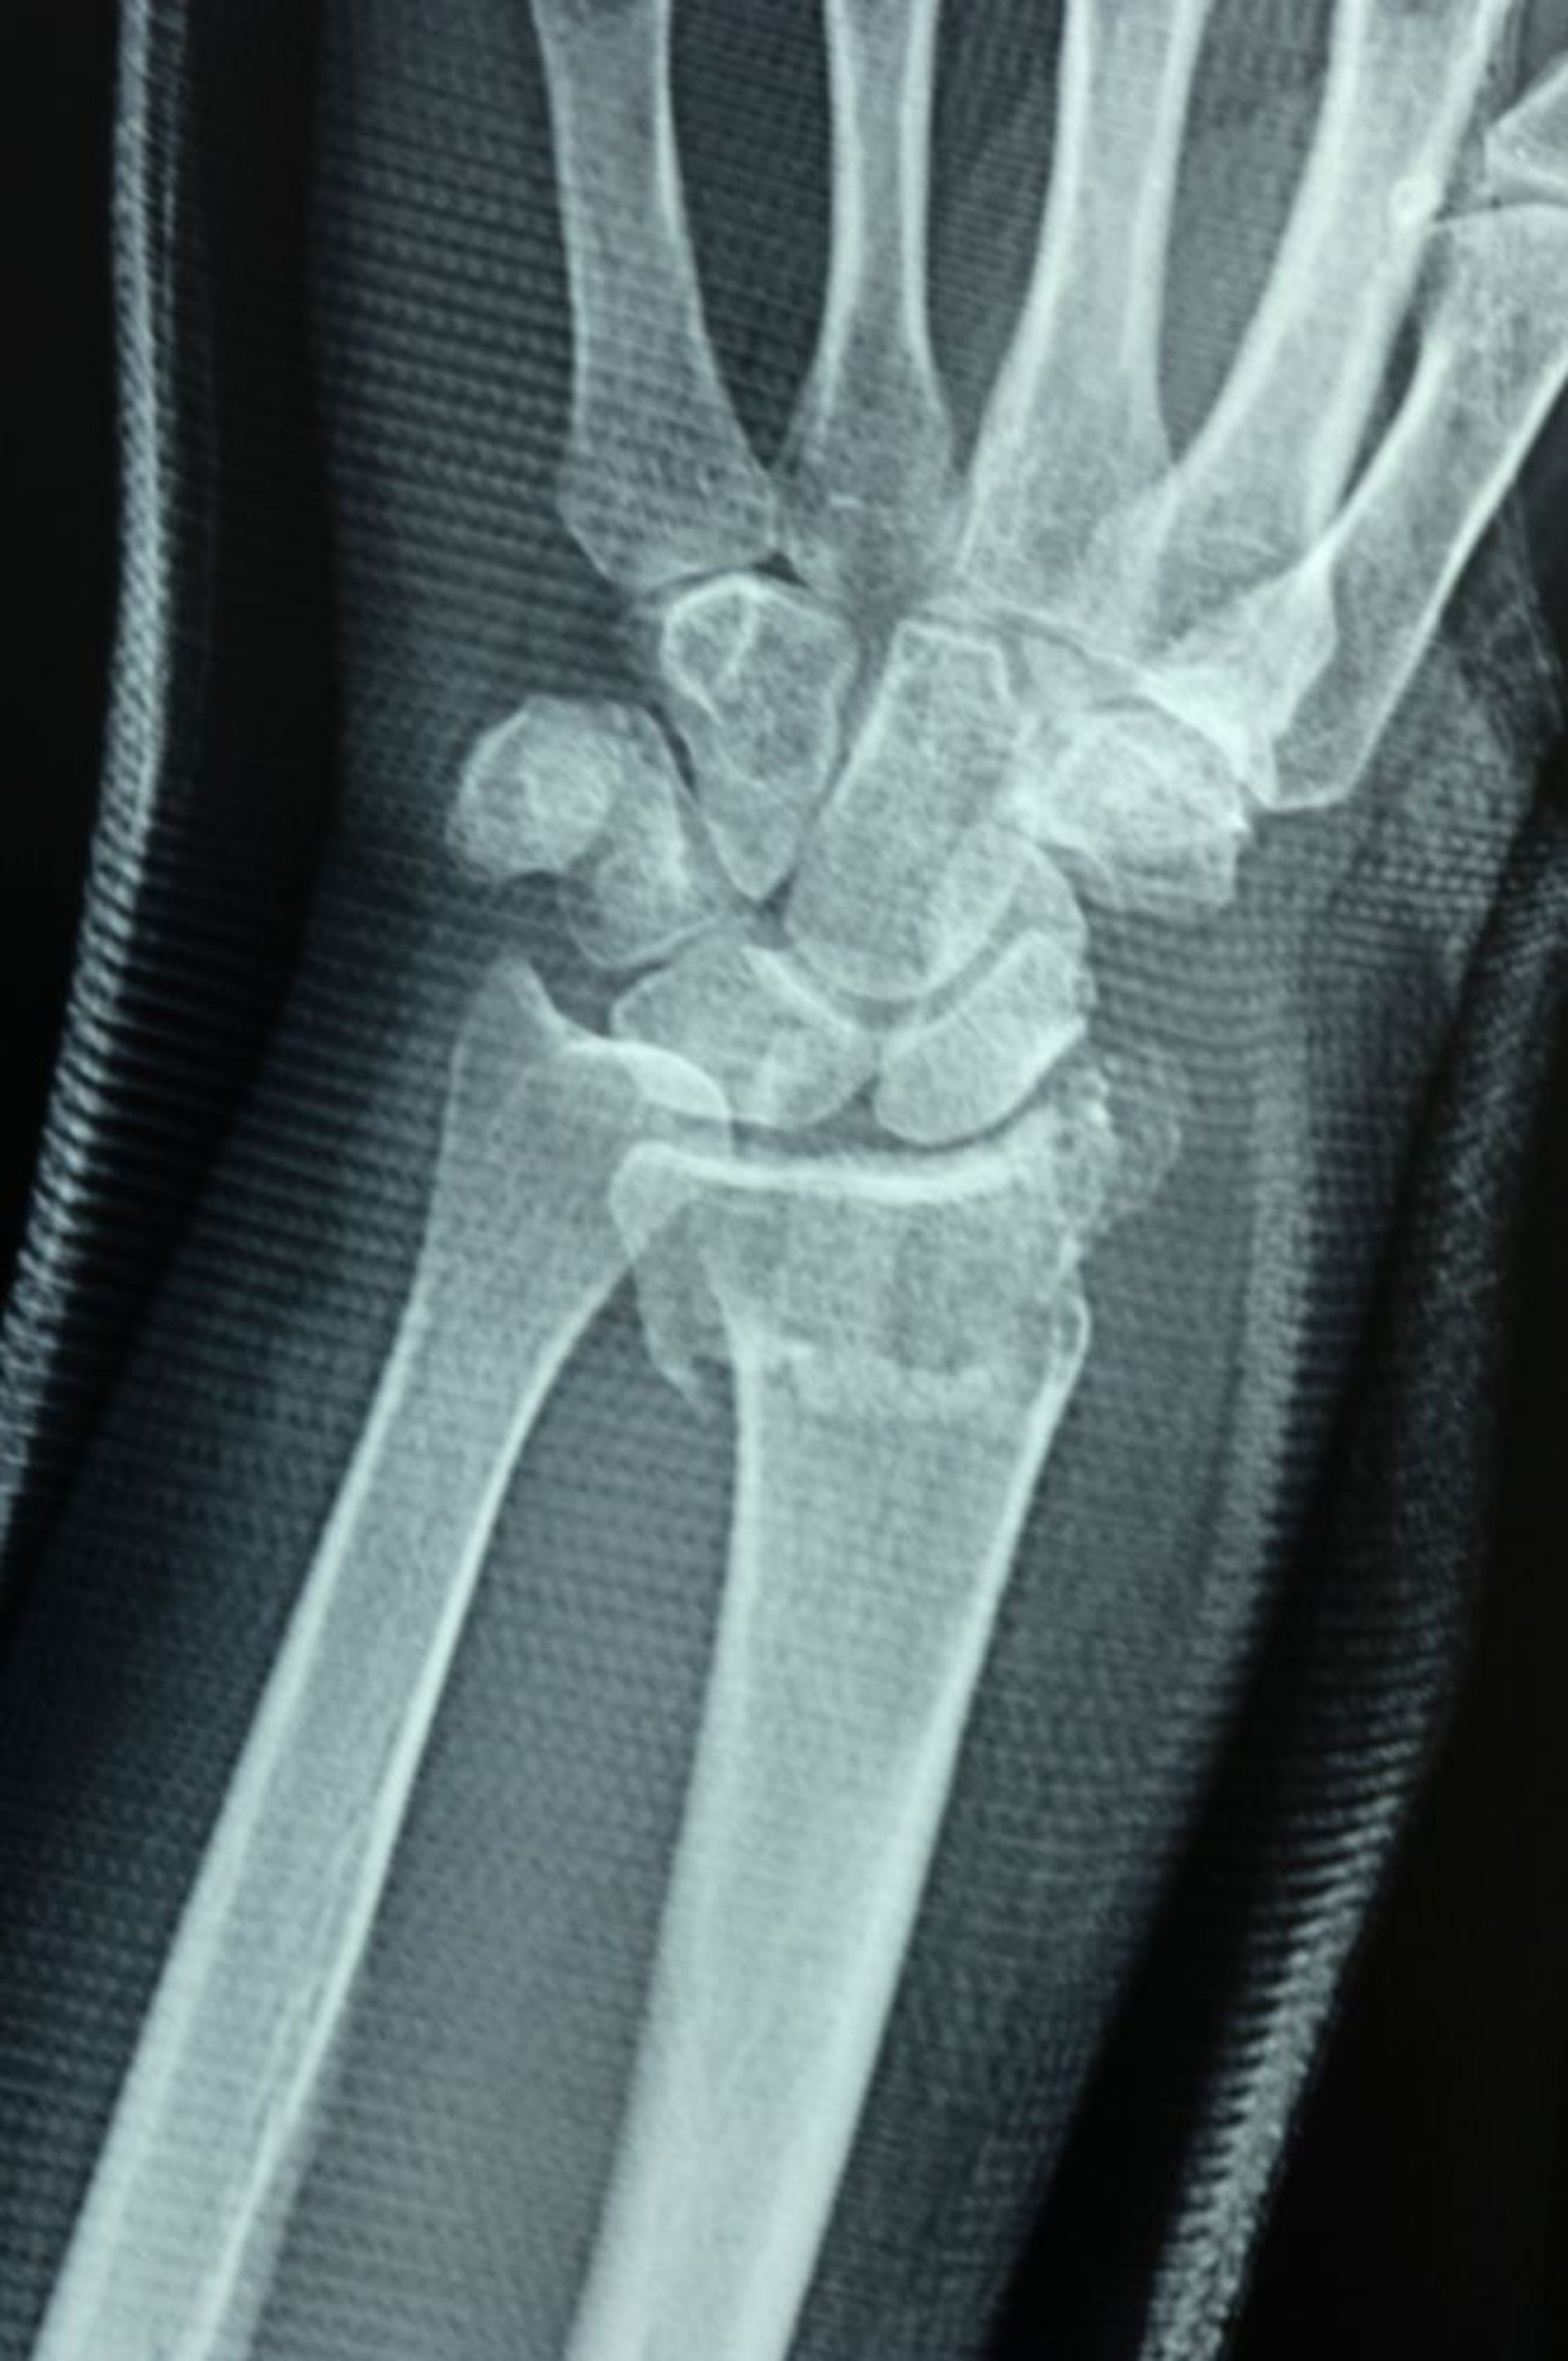

Fractura distal del radio

La articulación radiocubital se separa, lo que se demuestra por la falta de alineación de las superficies articulares del radio distal y el cúbito distal, lo que provoca un escalón.